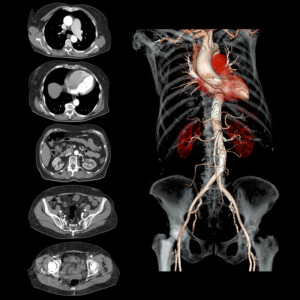

Ανευρύσματα, αρτηριοφλεβώδεις δυσπλασίες εγκεφάλου, στενώσεις, αποφράξεις αποτελούν μερικές από τις παθήσεις των αγγείων. Για την διάγνωση τους απαιτείται η διενέργεια μη επεμβατικής αγγειογραφίας του αντίστοιχου τμήματος όπως εγκεφάλου, τραχήλου, θωρακικής και κοιλιακής αορτής, λαγονίων αρτηριών, μηριαίων αρτηριών και άνω και κάτω άκρων. Για αυτήν την κατηγορία εξετάσεων απαιτείται η χρήση σκιαγραφικού μέσου.

Αποτελεί μια γρήγορη και ασφαλή μέθοδο για την απεικόνιση του πνευμονικού παρεγχύματος, των αγγείων αυτού, των οστών του θωρακικού κλωβού, του μεσοθωρακίου και της καρδιάς. Συχνές παθολογικές καταστάσεις που διαγιγνώσκονται με αυτή τη μέθοδο αποτελούν τα νεοπλάσματα πνεύμονα, οι λοιμώξεις των πνευμόνων(πνευμονίες), πνευμοθώρακας, αιμορραγίες κ.α.

Με την εξέταση αυτή ελέγχεται αν η ροή αίματος στις πνευμονικές αρτηρίες είναι ομαλή ή διακόπτεται (συνήθως από θρόμβο). Αυτή η μέθοδος είναι καταλυτική στην διάγνωση της πνευμονικής εμβολής, μιας κατάστασης απειλητικής για την ζωή του ασθενούς όπου διακόπτεται η ροή αίματος σε μικρά η μεγάλα αγγεία του πνεύμονα.